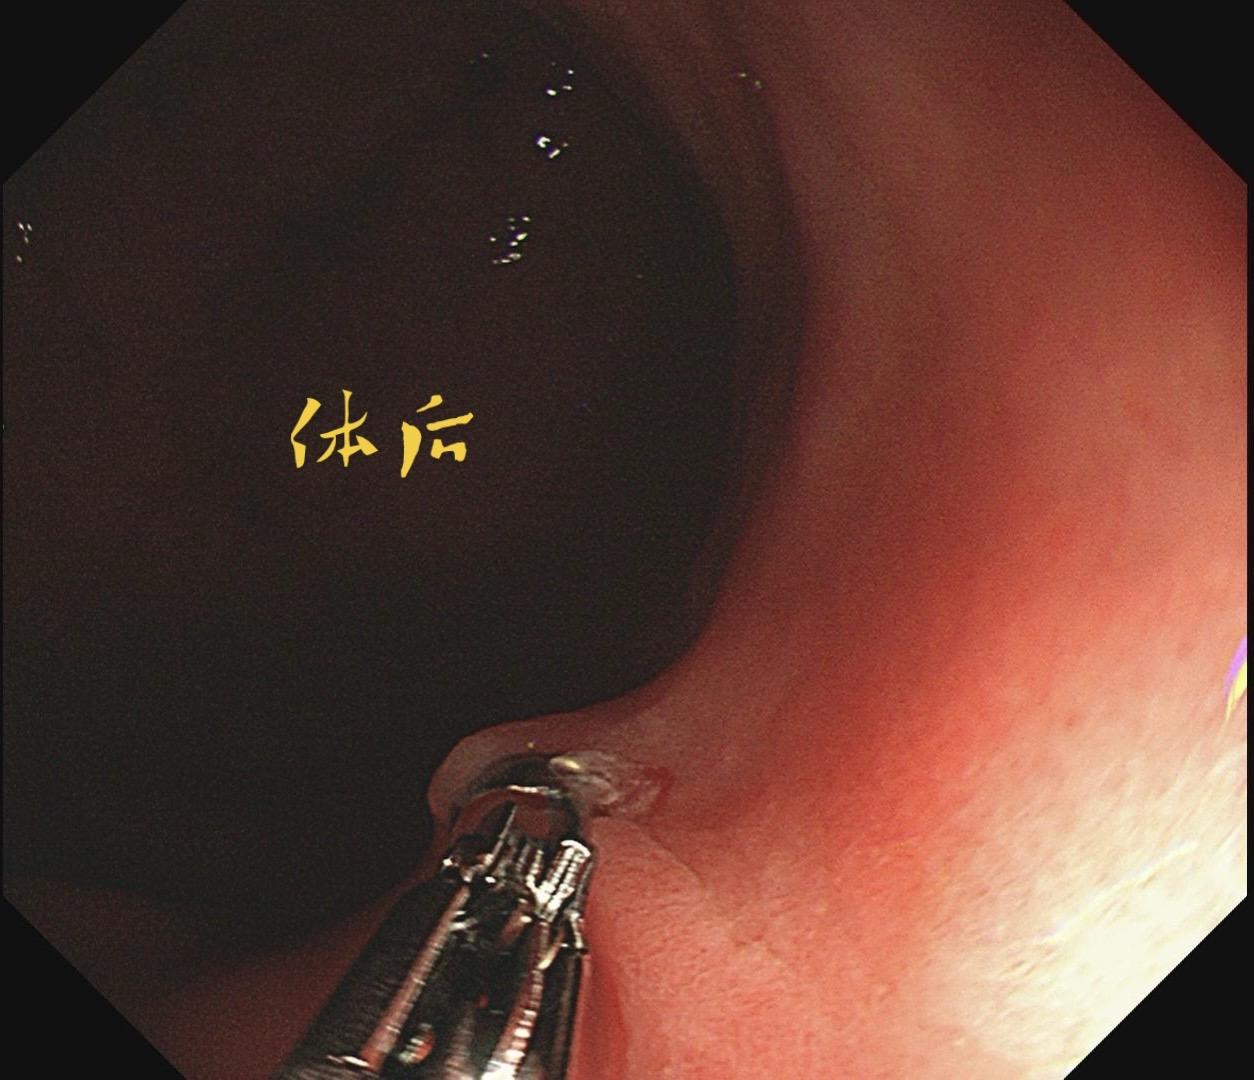

男,61岁,胃巨大褪色调病变。答案在最后一张图片,你猜对了吗? 患者因上腹部饱胀行胃镜检查,Hp阴性背景,胃窦至贲门下见一巨大褪色调病变,边界清晰,病变相对表浅,未见明显溃疡及隆起,胃壁较柔软,充气顺应性佳,予多点活检确诊,拟外科手术行全胃切除。做这么多年胃镜,还是第一次遇到这样的……